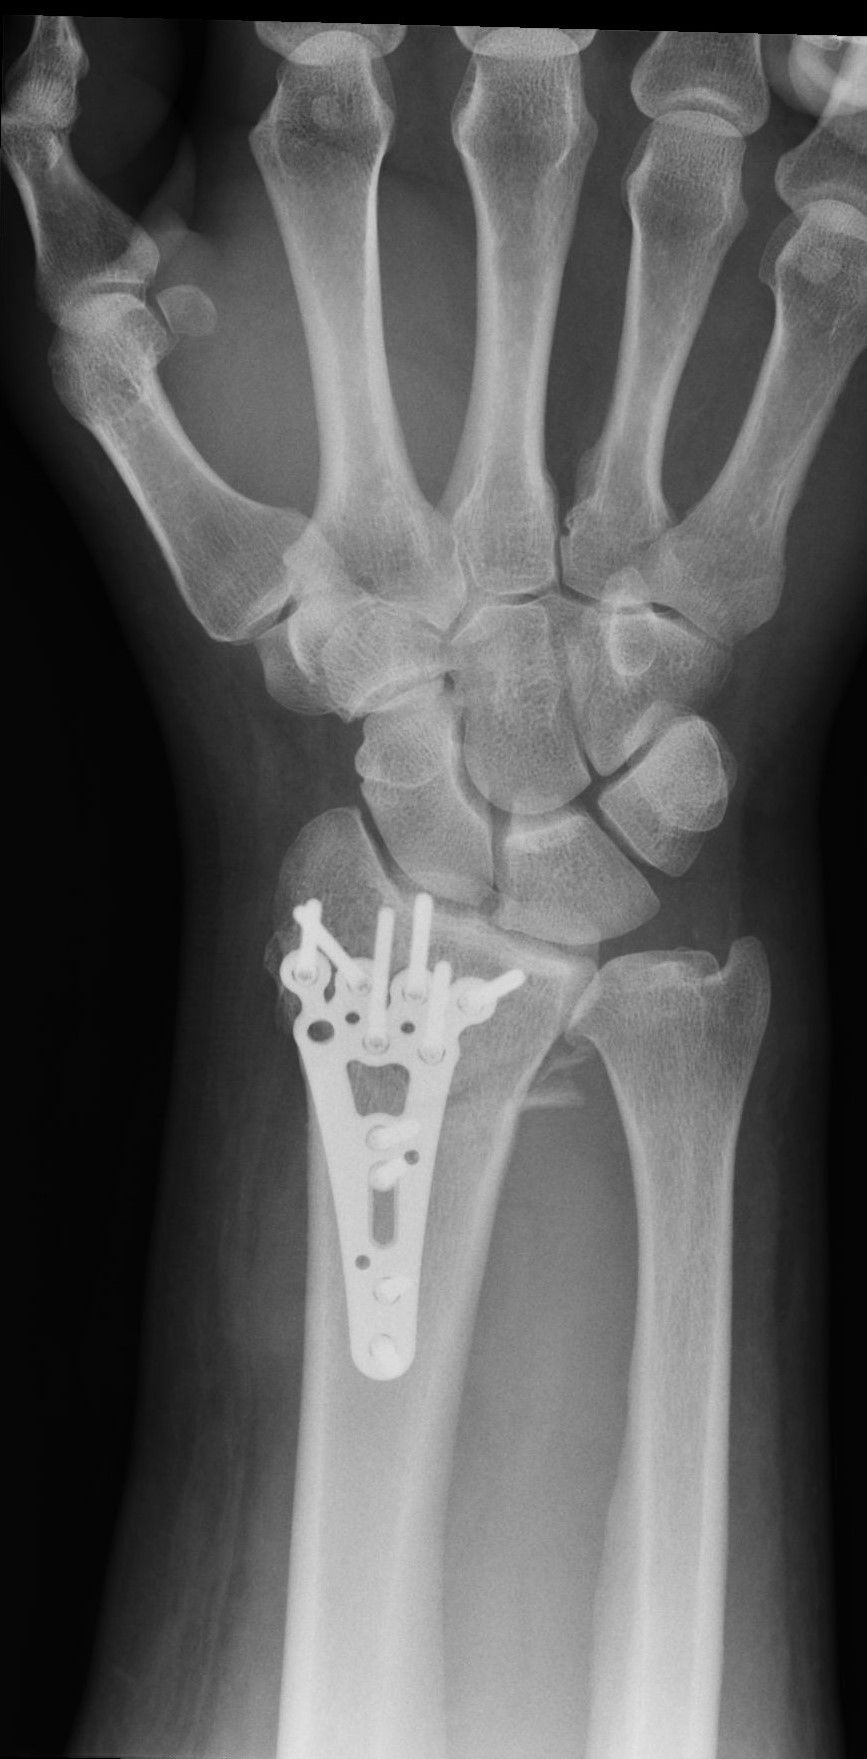

Interposition of the index flexor digitorum superficialis tendon beneath a fragment of the distal radius fracture: a case report

High-energy distal radius fractures are characterized by significant displacement of bone fragments, articular surface damage, and ligamentous injury. Tendon interposition between bone fragments occurs very rarely. In this report, we present a case of a complex distal radius fracture in which intraoperative findings revealed interposition of the flexor digitorum superficialis tendon of the index finger beneath one of the fracture fragments. The exceptional rarity of this situation prompted the authors to report this case.